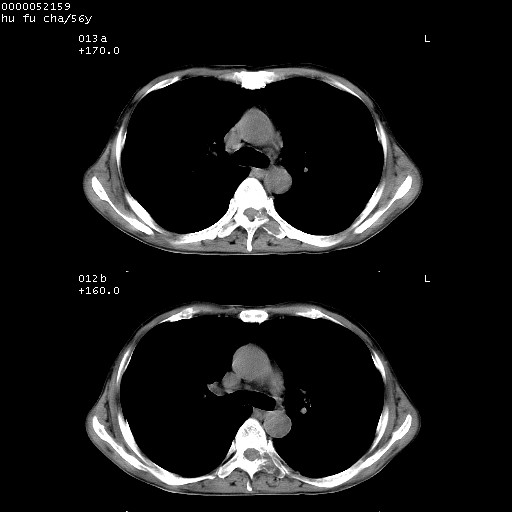

以下是引用zsl6918在2008-8-25 22:47:00的发言:[br]胸骨,胸椎及肋骨均可见多发转移表现,肝内低密度结节不除外转移。原发灶可能在右肺。双侧可见支扩表现。